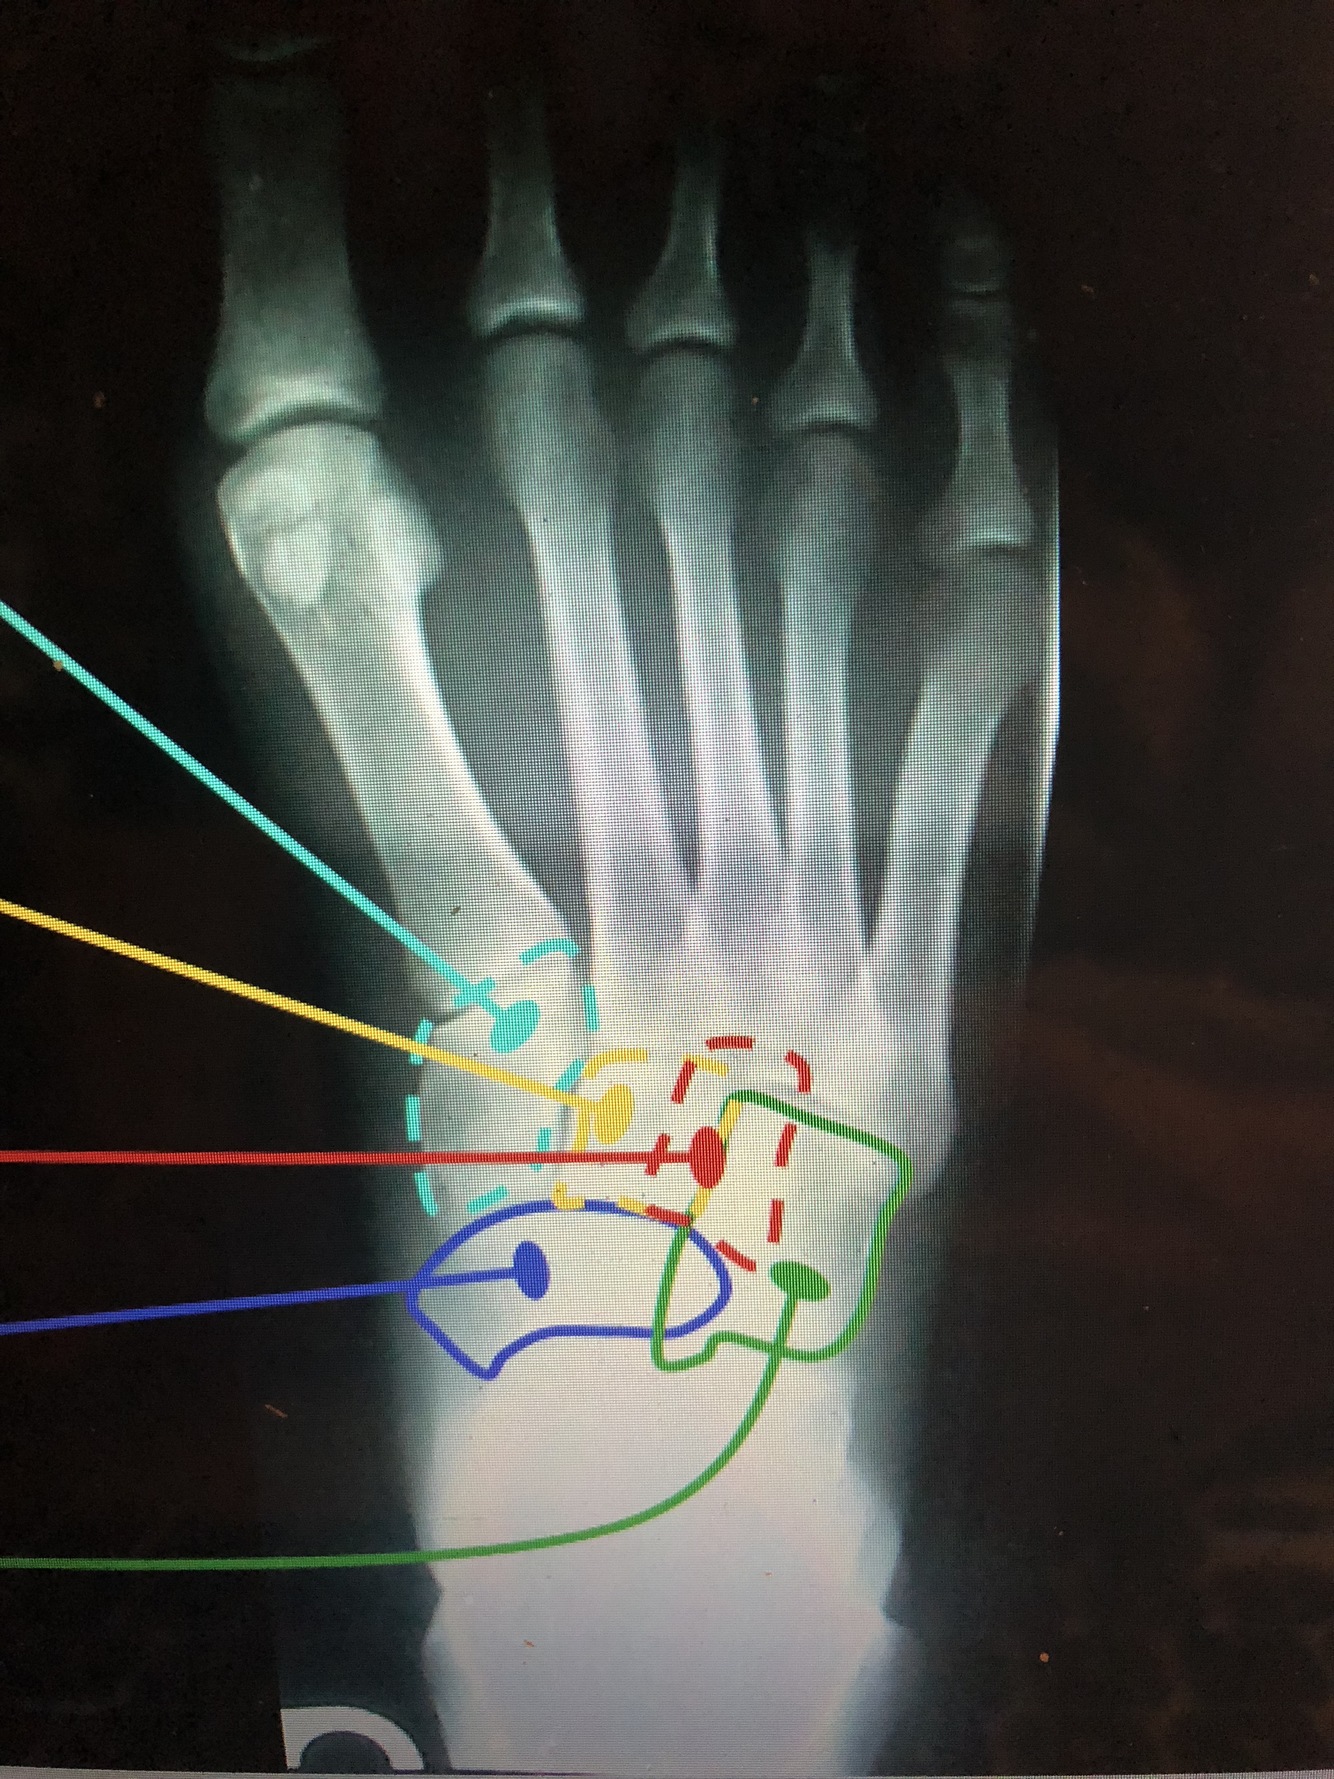

What bone is light blue?

Medial Cuneiform (1st)

What bone is yellow?

Intermediate Cuneiform (2nd)

What bone is red?

Lateral Cuneiform (3rd)

What bone is blue?

Navicular

What bone is green?

Cuboid

Which phalange is which color?

Dark blue - distal second phalange

Red - middle second phalange

light blue - proximal second phalange

What part of the phalanges are what color?

red - head of second phalange

dark blue - base of second phalange

light blue - Distal Ungual tuft